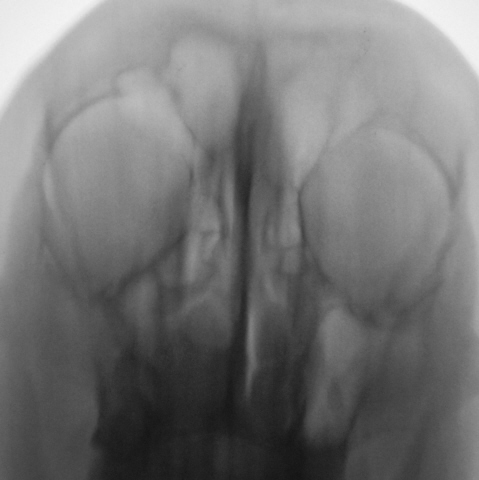

Ваше мнение коллеги по представленным снимкам и томограммам. Каждая иллюстрация представлена в двух вариантах - без обработки изображения и с "обработкой".

Четко не представляю. ) Случай интересный. Вероятно у него есть богатый анамнез с оперированной фиброзной дисплазией латеральной стенки пазухи? Какой не понять, снимки перевернуты.

Да. Перевернуты только томограммы, на которых левая сторона слева, а правая - справа. В анамнезе была операция, какая, пациент уточнить не может. В настоящее время  появились боли распирающего характера слева, чувство заложенности, направлен на исследование "без диагноза".